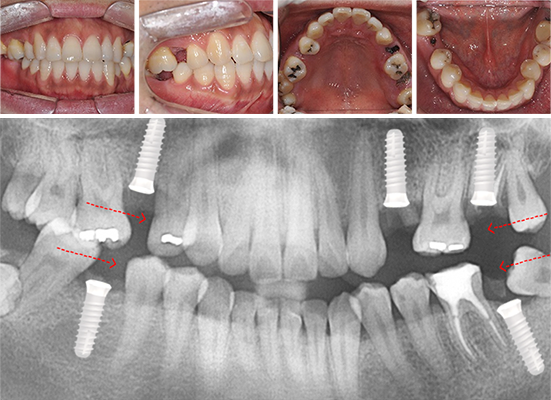

30대 남환으로 다른 치과에서 임플란트 5개 진단을 받고 내원. 교정과 협진으로 공간을 메꾸고 오른쪽 위 치아에 임플란트를 1개만 식립하여 자연치아를 최대한 활용하는 진료 계획을 세움.

다른 병원에서 임플란트 5개 진단을 받고 내원

사랑니를 빈 공간으로 이동시킴

치아가 상실된 부위 공간을 사랑니를 활용하여 모두 메워 임플란트 개수를 5개에서 1개로 감소. 또한 상실된 부위의 잇몸 뼈 높이가 높아져 예전보다 건강해 졌으며, 입술 외모가 개선되었습니다.